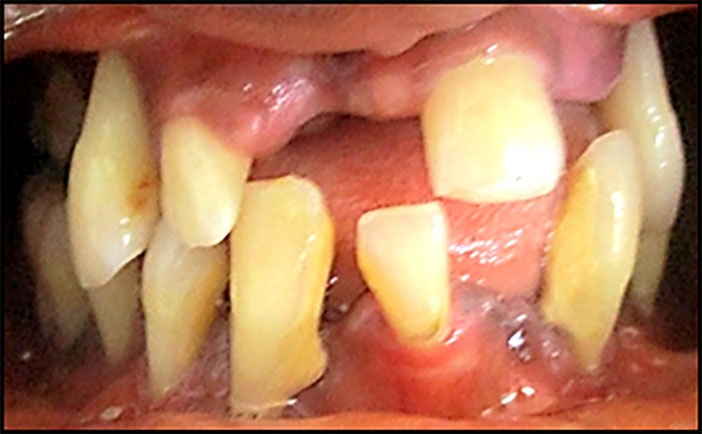

The significant variables selected for analysis by logistic regression, shown in Table 3, were: variables not related to periodontal status: age, socioeconomic status, smoking habits, brushing frequency and variables related to periodontal status: teeth lost and mobile teeth. Having at least 5 mobile teeth (OR= 4.11, 95% CI: 2.95‒5.73, P=0.000), and/or 5 missing teeth (OR=2.60, 95% CI: 1.85‒3.66, P=0.000) were identified as independent risk indicators for severe periodontitis (Figures 2 and 3).

japid-14-7-g002

Figure 2. Clinical front view of generalized severe periodontitis (Stage IV / Grade C) of a 18 year patient. Note the presence of attachment loss, dental migration/mobility, and missing teeth: destruction exceeds expectation given biofilm deposits.

Figure 3. A panoramic X-ray of the patient presented in figure 1. Note severe generalized radiographic bone loss extending to the apical third of the root: % bone loss/age (100% / 18 = 5.5) > 1.0